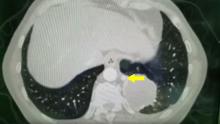

This video demonstrates a uniportal VATS left lower lobectomy to treat intralobar sequestration. Special attention should be given to the arterial branch that feeds the tumor during dissection. The arterial branch usually comes directly from the descending aorta.